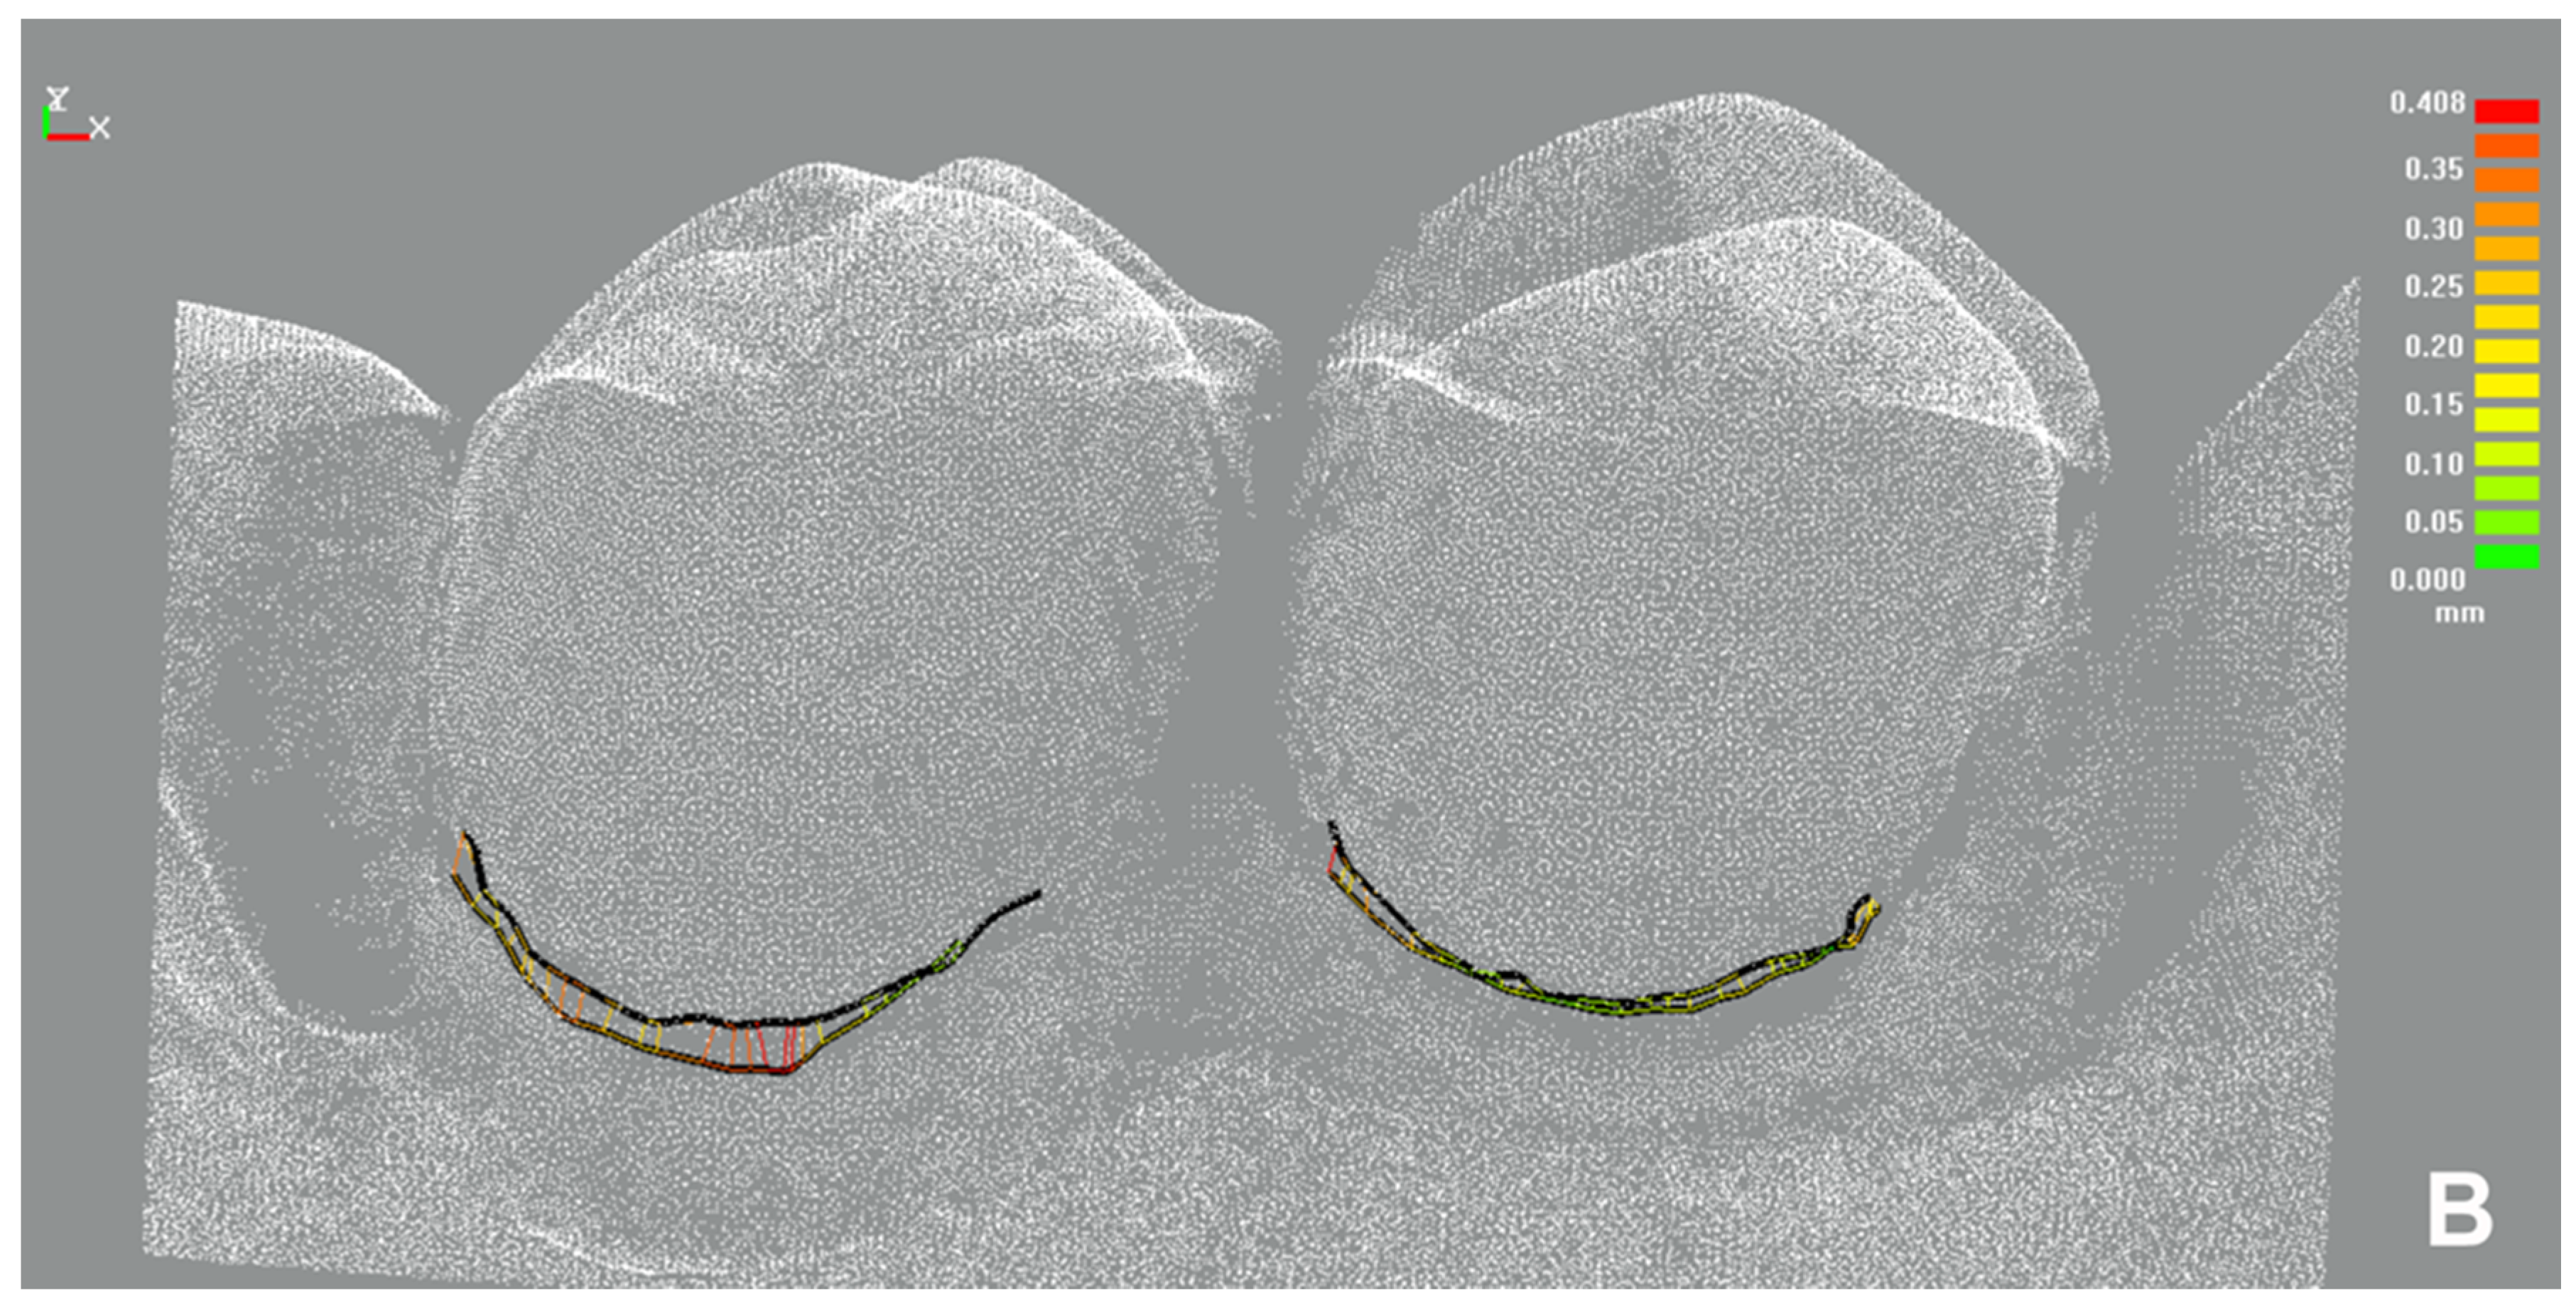

3.5.3. Marginal Gingiva Height Change (Secondary Outcome)-t-Test for Dependent Samples

| Sulcus Representation | Marginal Gingiva Height Change | |

|---|---|---|

| Mean RMS Error ± SD | 14.6 µm ± 4.5 | 20.5 µm ± 8.2 |

| Percentage of RMS Errors Below the Threshold of 32 µm | 100% | 96.3% |